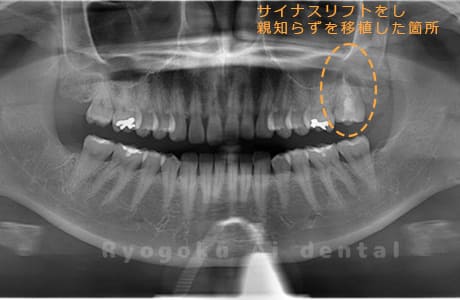

Case26

歯軋りが原因で奥歯を割ってしまった患者様です。下の親知らずを移植し、その際にサイナスリフトを行いました。問題なく経過し、患者様も大変満足されていました。